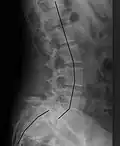

| X-ray of the lateral lumbar spine with a grade III anterolisthesis at the L5-S1 level | |

Spondylolisthesis refers to a condition in which one spinal vertebra slips out of place compared to another.[1] While some medical dictionaries define spondylolisthesis specifically as the forward or anterior displacement of a vertebra over the vertebra inferior to it (or the sacrum),[2][3] it is often defined in medical textbooks as displacement in any direction.[4][5]

Spondylolisthesis is graded based upon the degree of slippage of one vertebral body relative to the subsequent adjacent vertebral body.[6] Spondylolisthesis is classified as one of the six major etiologies: degenerative, traumatic, dysplastic, isthmic, pathologic, or post-surgical.[7] Spondylolisthesis most commonly occurs in the lumbar spine, primarily at the L5-S1 level, with the L5 vertebral body anteriorly translating over the S1 vertebral body.[7]